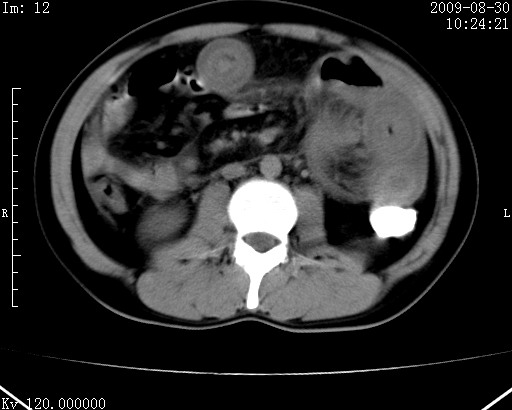

患者唐某,男31岁,已婚,本地务农。

自述入院前两天一次进食较多冷饮之后,出现阵发性上腹部疼痛,次日加剧伴恶心、呕吐,呕吐后症状稍减轻。食欲差。大便每天1-2次,量少,暗红色水样。小便赤。无畏寒、发热、咳嗽等呼吸道症状。无高血压及胃病史。

检查:体温、血压及脉搏正常.皮肤无黄染,浅表无淋巴结肿大。左腹肌紧张,左上腹有压痛,无反跳痛,可触及包块。

生化:钾、钠、氯、钙、ph正常,总胆红素和直接胆红素稍高,空腹血糖稍高。

尿淀粉酶:1256 u/l(正常60-401)。

血常规:wbc 22.4x109/l gr88% ly9.6%其余基本正常。

胃镜:急性胃炎。立位腹平片:未见异常。

下面是ct平扫,降结肠内是对比剂。

术前影像诊断:上段空肠急性缺血性坏死并腹水。建议手术治疗。

术中见上段空肠约70cm长范围坏死,从屈氏韧带远端约10cm处开始。坏死肠管肿胀变形变色,管壁明显环形增厚,部分聚成大肿块,无扭转和套叠。肠系膜上动脉分支内广泛泥沙状血栓。肠切除。

临床诊断:肠系膜上动脉梗塞并急性肠坏死。

开始时我们科也有人认为是套叠,最后统一意见,不考虑肠套。我们看到的“靶征”,“晕圈征”,“双圈征”实际上只是单根肠管的横断面。坏死肿胀后肠壁各层的密度不一样。

左侧腹小肠腔管壁明显增厚,部分内示靶征,走行异常,部分肠系膜绳样改变,肝包膜下及肠间较多液体密度,然梗阻近端肠腔积气不明显。

考虑;肠扭曲伴肠坏死。